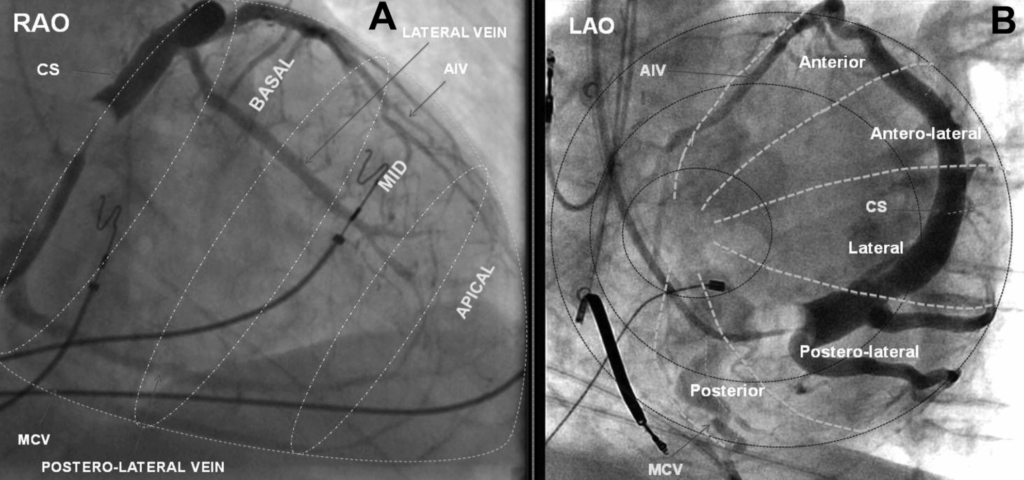

The first thing to visualize carefully is the anatomy of the coronary sinus in RAO 30° and LAO 30° (ideally 40°).

In the RAO view, the atrium appears on the left side of the screen and the ventricle on the right.

This projection helps determine whether a structure is basal, mid, or apical.

The coronary sinus ostium is located posterior to the tricuspid valve annulus.

From this posterior–basal region, the coronary venous system branches as follows:

• Middle cardiac vein – runs along the posterior interventricular groove.

• Posterolateral vein – courses toward the posterolateral left ventricular wall. (PRIMARY TARGET for LV pacing in CRT.)

• Lateral (marginal) vein – follows the lateral left ventricular wall. (KEY target for LV pacing.)

• Anterolateral vein – projects toward the anterolateral wall.

• Great cardiac vein – ascends in the anterior interventricular groove and then continues toward the coronary sinus.

In the LAO view, you visualize the two “discs” of the right ventricle, with the right-sided structures on the left of the screen and the left-sided structures on the right.

The LAO view is essential, because it allows you to assess whether your chosen LV pacing site is likely to deliver good long-term CRT response.

Practically, you target lateral venous branches located between 2 and 5 o’clock, ideally the posterolateral or lateral veins, which usually provide the most favorable electrical and mechanical delay.